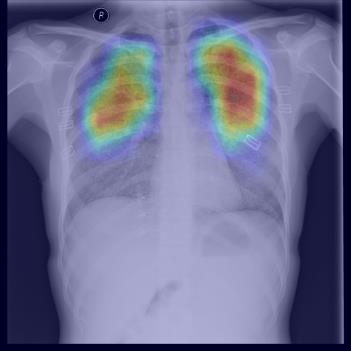

Chest X-ray (CXR) is the most typical diagnostic X-ray examination for screening various thoracic diseases. Automatically localizing lesions from CXR is promising for alleviating radiologists' reading burden. However, CXR datasets are often with massive image-level annotations and scarce lesion-level annotations, and more often, without annotations. Thus far, unifying different supervision granularities to develop thoracic disease detection algorithms has not been comprehensively addressed. In this paper, we present OXnet, the first deep omni-supervised thoracic disease detection network to our best knowledge that uses as much available supervision as possible for CXR diagnosis. We first introduce supervised learning via a one-stage detection model. Then, we inject a global classification head to the detection model and propose dual attention alignment to guide the global gradient to the local detection branch, which enables learning lesion detection from image-level annotations. We also impose intra-class compactness and inter-class separability with global prototype alignment to further enhance the global information learning. Moreover, we leverage a soft focal loss to distill the soft pseudo-labels of unlabeled data generated by a teacher model. Extensive experiments on a large-scale chest X-ray dataset show the proposed OXnet outperforms competitive methods with significant margins. Further, we investigate omni-supervision under various annotation granularities and corroborate OXnet is a promising choice to mitigate the plight of annotation shortage for medical image diagnosis.